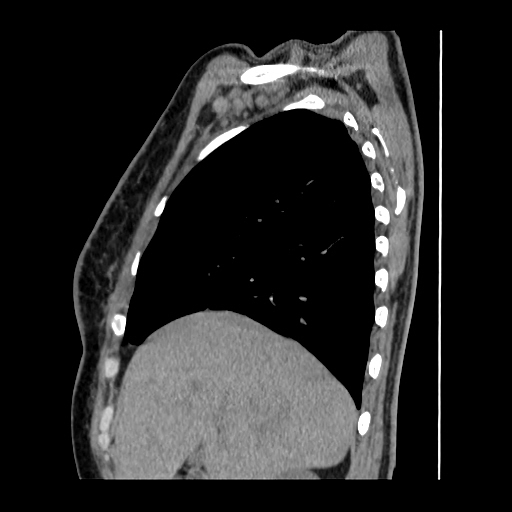

A 62 years old man with enlarged mole on chest since 2 months.

CT chest :-